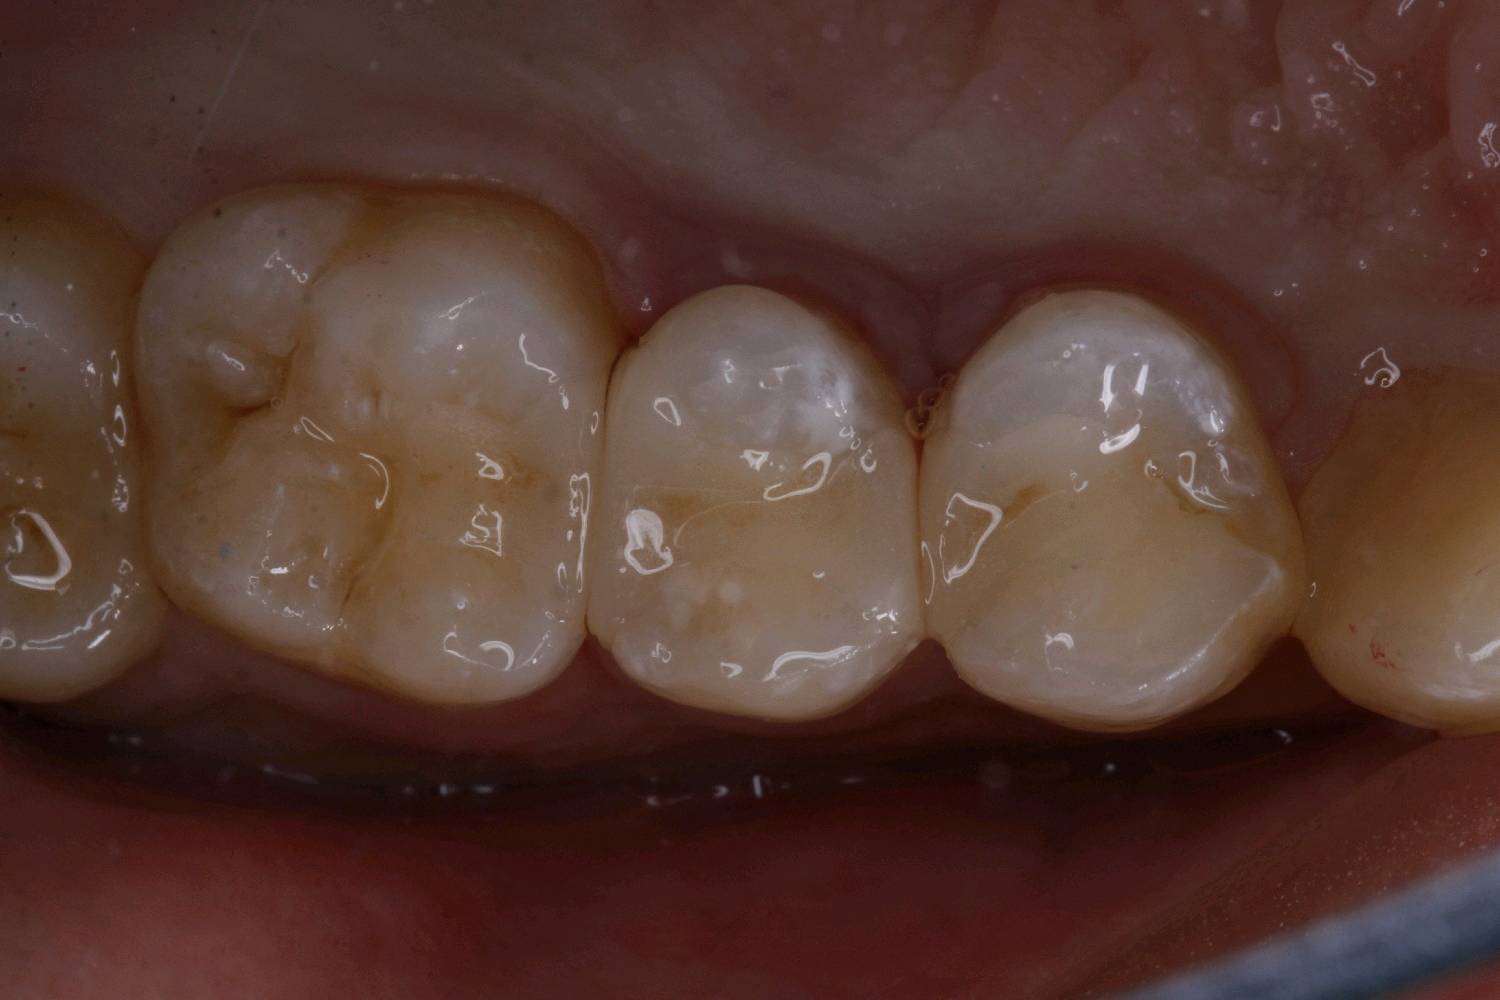

食物嵌塞为细菌提供了良好的滋生环境,容易导致细菌大量繁殖,产生酸性物质,从而增加蛀牙的风险。最好是用嵌体修复,能更好的恢复牙体的形态和功能。想要有一口好牙齿,做起来也不难。但是,单单口腔清洁这件小事,大多数人都没做好。你以为刷遍了牙齿的每个角落,但可能只刷了一半的牙。刷毛无法有效进入牙缝隙刷牙后仍有食物残渣等残留于牙齿邻面部位导致邻面龋坏。平时不易察觉,需要定期检查,为了更恢复邻接关系,预备制作嵌体,更好的恢复了牙体形态,增加了固位力,恢复正常的邻接关系,可以得到更好洁。基牙预备后,通过德国西诺德 CEREC ,当日完成即可佩戴,患者满意。